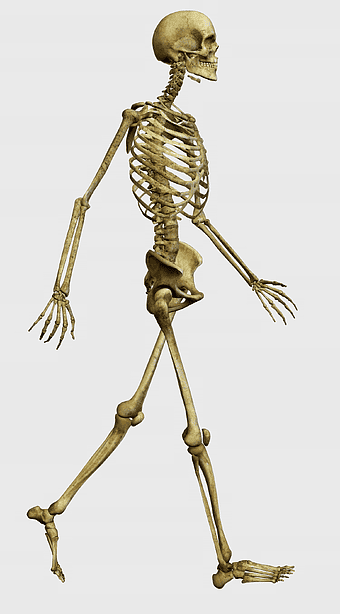

walking human skeleton, human anatomy illustration, skeleton hand in motion, long bone structure, skeletal movement analysis, anatomical walking pose, fantastically detailed skeleton -